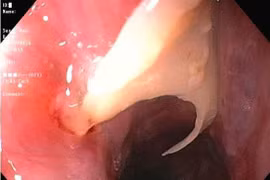

Phát hiện xương cá 5 cm đâm thủng ruột non sau 5 ngày đau bụng

Xương cá là dị vật thường gặp và nhiều người chủ quan. Dị vật có thể xuyên thủng thành dạ dày hoặc ruột, gây áp xe ổ bụng, viêm phúc mạc, nhiễm trùng huyết.